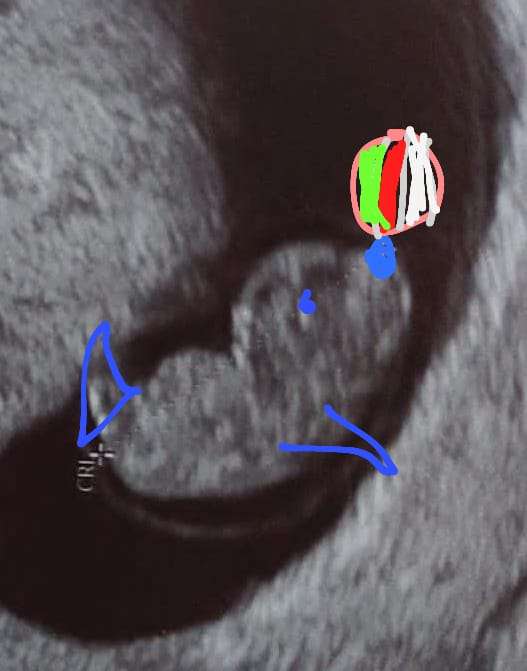

Gratuluję, ale już dorodny bąbelekHeja! My już po wizycie. Prawie 2cm, serduszko 172/min, powiedziała że nie ma żadnych zastrzeżeń że wszystko wygląda dobrze tam w środku. 8+4 potwierdzone więc poród na przełomie listopada/grudnia.

faktycznie kształt fasolkiHeja! My już po wizycie. Prawie 2cm, serduszko 172/min, powiedziała że nie ma żadnych zastrzeżeń że wszystko wygląda dobrze tam w środku. 8+4 potwierdzone więc poród na przełomie listopada/grudnia.